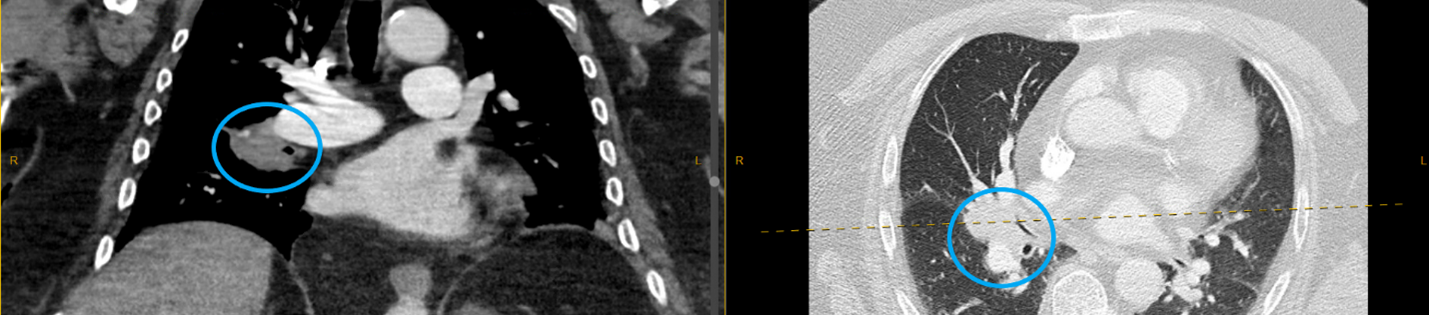

An elderly male with a complex past medical history presented to the Emergency Department with the primary complaint of chest tightness for 2 days. He denied symptoms of diaphoresis, nausea, shortness of breath, palpitations, light-headedness, productive cough, dyspnea, chest pain, fevers, chills, or hemoptysis. He had no known sick contacts or recent travel. A computer tomography (CT) scan of the thorax showed a right hilar mass (Image 1). He underwent a bronchoscopy and right hilar transbronchial needle aspiration (TBNA) and bronchoalveolar lavage (BAL) were collected. The pathology report indicated abnormal lymphocytic proliferation, concerning for a mature small B-cell lymphoproliferative disorder.